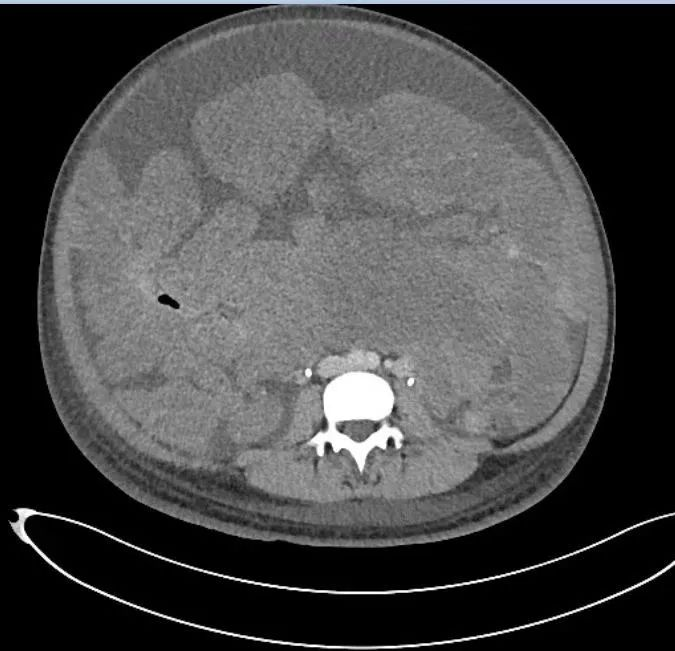

谭先杰医生 图 当小曼的CT片子一张一张被贴在阅片灯箱上之后,我沉默了报告上写道:盆腹腔巨大融合性分叶状包块,下端达盆底,上端达剑突,肠管表面及肠系膜间多发低回声结节,无法计数…… 小曼看过当地多家医院,还去了省城的大医院,但都被告知已经无法手术,他们让小曼到北京的协和医院看看还有没有办法。

小曼的腹部CT片,灰度稍高的不规则团块均为肿瘤,谭先杰医生 图 在围绕小曼的MDT中,来自兄弟科室泌尿外科、基本外科、血管外科和平台科室麻醉科、手术室、输血科、放射科、重症监护室(ICU)的专家,一起分析讨论了小曼的病情。